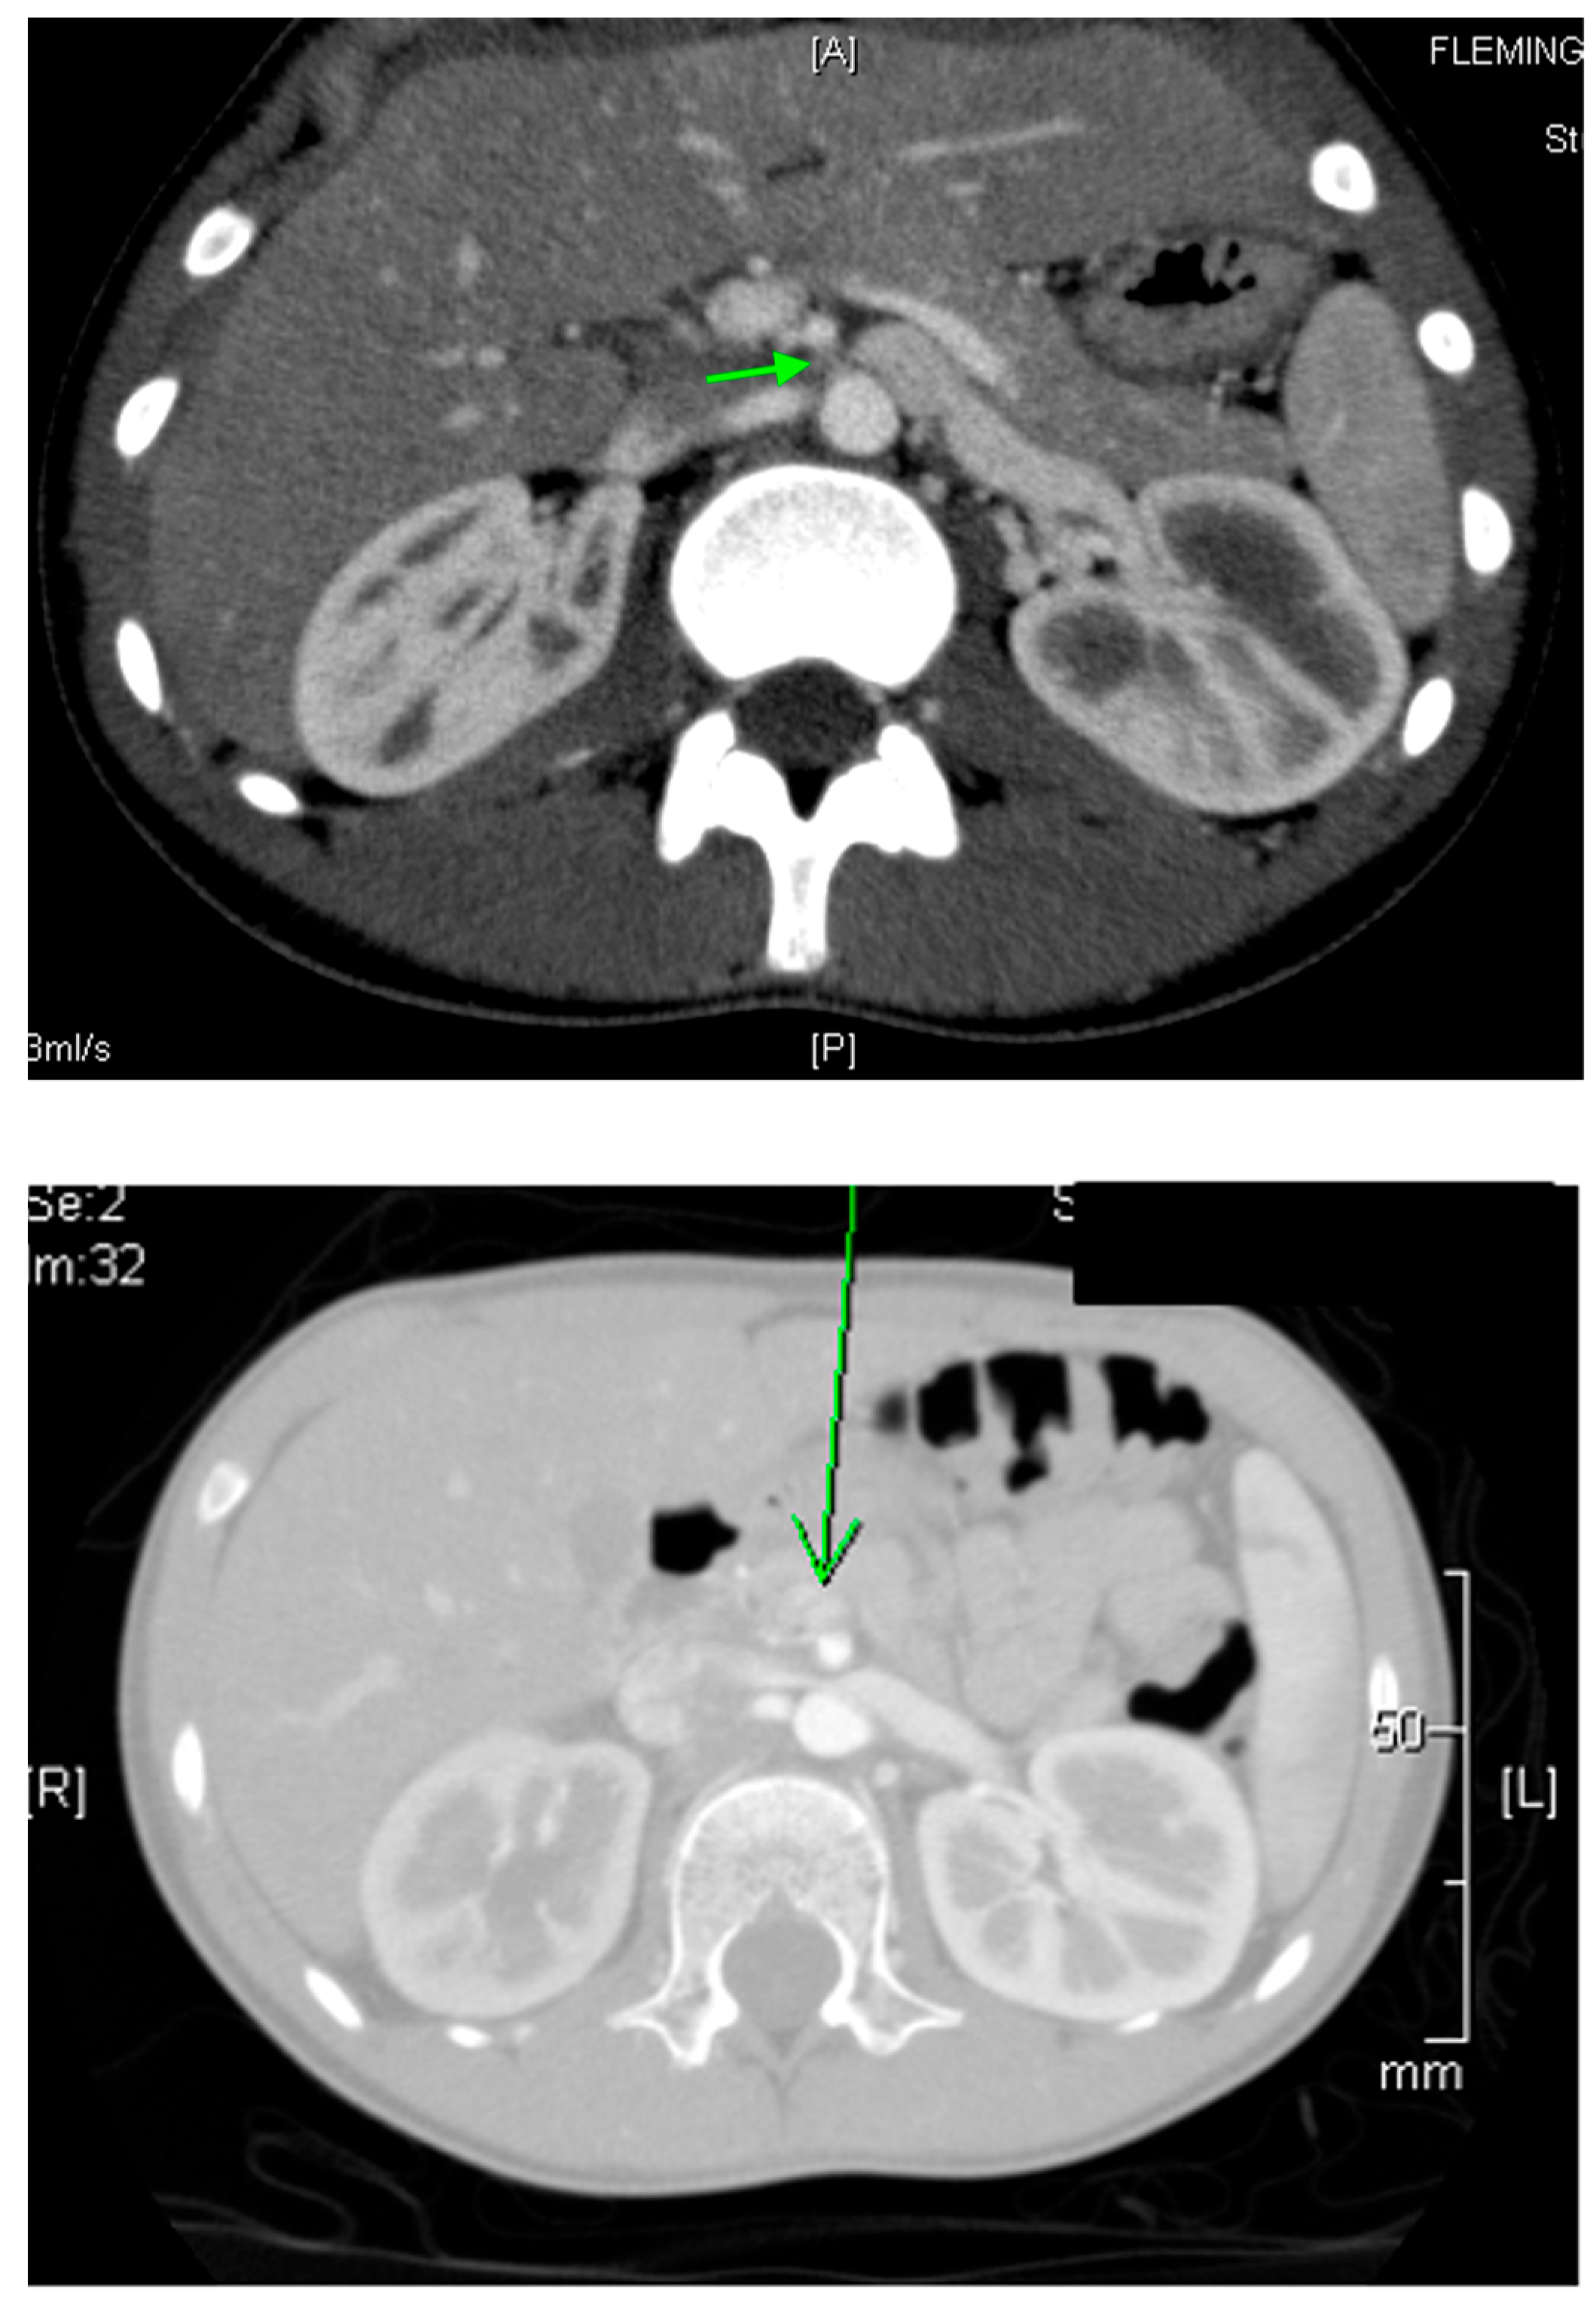

22.3. Nutcracker Syndrome